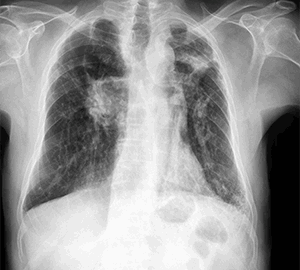

Masculino 75 años, APP: TBC, MC: Tos productiva crónica y disnea.